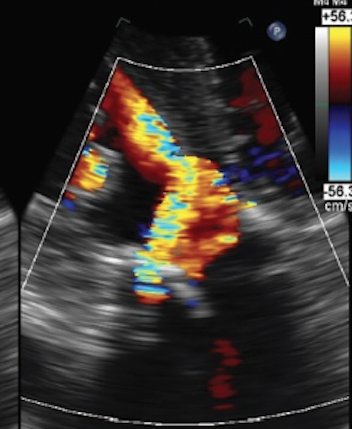

Amar Krishnaswamy, MD: As with most things, looking at it from different angles is always best. We generally look at degree of paravalvular regurgitation in 3 different ways in our practice in Cleveland Clinic. One is with aortography to understand the PVL degree in that way. The second is with echocardiography, and because all of our cases are done under conscious sedation, that echocardiogram is a transthoracic echo. Our echo techs are fantastic and it is frankly rare, if ever, that they can't get diagnostic quality imaging, irrespective of patient factors. The third method involves looking at invasive hemodynamics. We always measure the pressures in the ventricle and the aorta before and after valve deployment. There are clues in each of these three things, aortography, echo, and hemodynamics, to help us put together whether this patient has mild PVL, moderate, or severe, and help us decide what we should do about it.